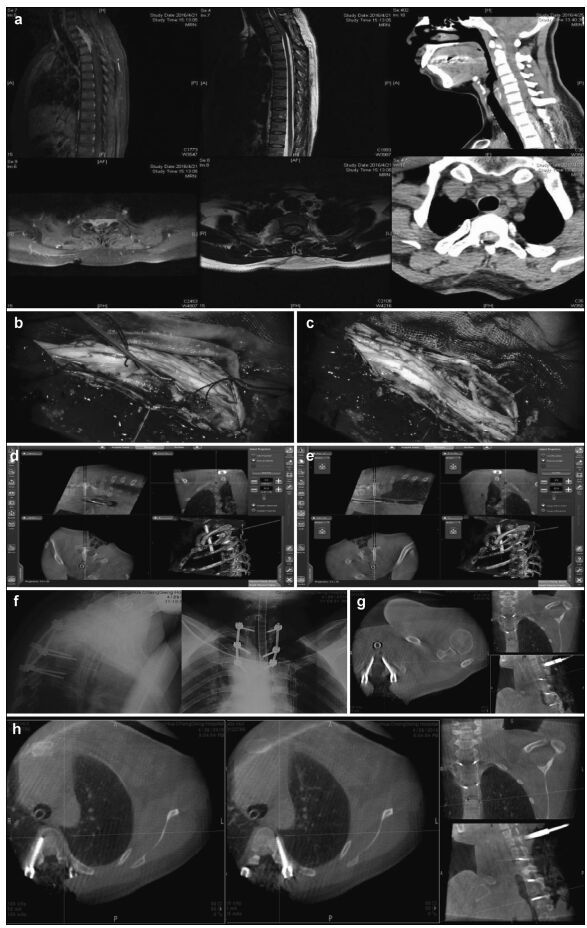

For the thoracic/lumbar/sacral pedicle internal fixation group, 148 pedicle screws were implanted under navigational guidance. Intraoperative O-arm 2D lateral scans did not show screw position deviations, but the 3D scans found 148 Richter grade Ⅰ screws (0 screws penetrating the pedicle) and 4 grade Ⅱ screws that had deviated to the lateral pedicle (Figures 2-5).Intraoperative O-arm 3D scans were repeated for confirmation. Secondary correction was performed under navigational assistance, yielding a final accuracy of 97.3% (144/148).

| Figure 2 Preoperative, intraoperative, and postoperative images of patients in the thoracic intraspinal meningioma resection and pedicle screw fixation group. (a) Cervical thoracic vertebrae computed tomography shows a high-density tumor shadow in the thoracic spinal canal (T1-T4). Magnetic resonance imaging shows T2 image isointensity in the spinal canal (T1-T4). An enhanced scan shows a significantly enhanced area located in the ventral spinal cord that has invaded the intervertebral foramen. (b) Intraoperative microscopy shows a spinal cord ventral tumor, originating in the dura mater. (c) Intraoperative microscopy shows nearly total resection of the spinal cord ventral tumor, with the spinal cord remaining intact. (d, e) Intraoperative T2 pedicle screw implantation is performed under real-time navigation. The entry direction, angle, and depth of the screw is according to the navigation plan. (f, g, h) After screw implantation, an O-arm two-dimensional lateral scan shows good screw positioning. The O-arm three-dimensional scan found that the T1 bilateral pedicle screws are well positioned and do not penetrate the bone cortex. The T4 left pedicle screw position is also good. The left pedicle screw is in the lateral vertebrae, and no lung injury is seen between the vertebral body and rib. The screw position was not adjusted intraoperatively because it is within the acceptable range. |